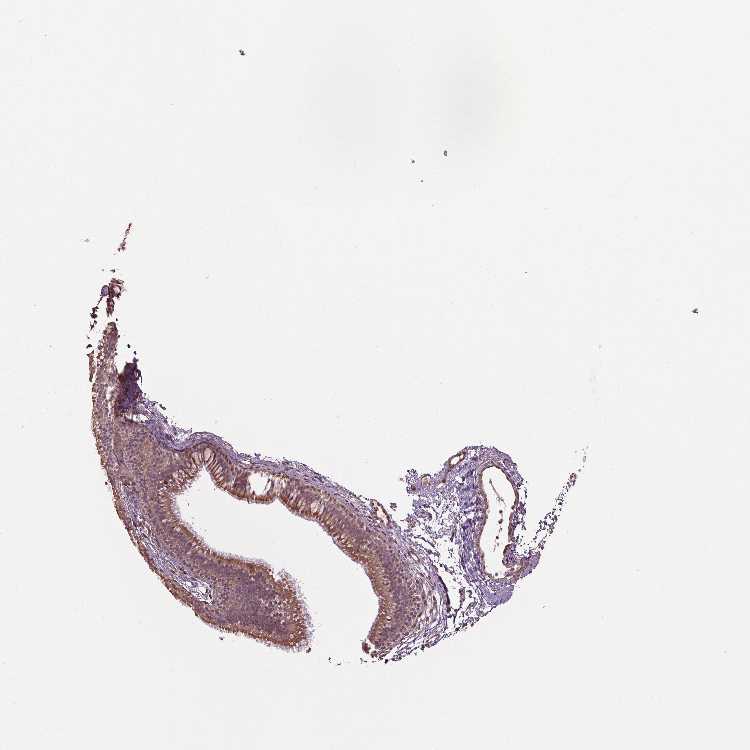

RNPEP